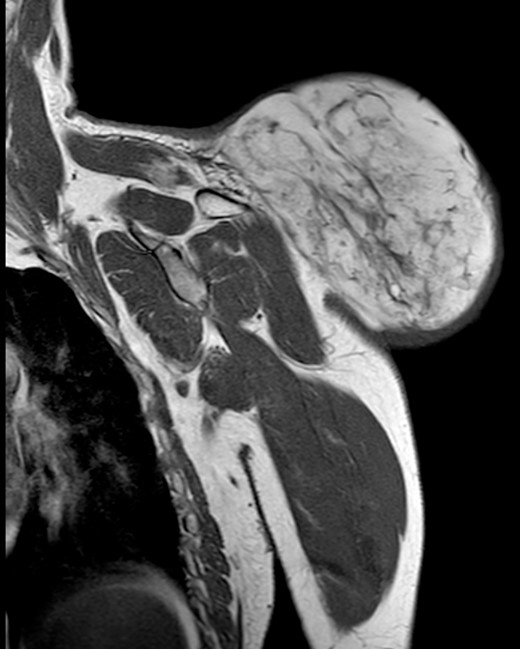

During the follow-up, a magnetic resonance (Figs 3 and 4) was performed describing a soft tissue lesion highly suggestive for liposarcoma as a first possibility diagnosis, with an addition image suggesting metastatic axillary lymph node. After the imaging results, biopsies were taken and analysed by the pathologist with a final diagnosis of PL.

Magnetic resonance imaging T1: polylobulated lesion with multiple septa separating different areas of fat tissue.